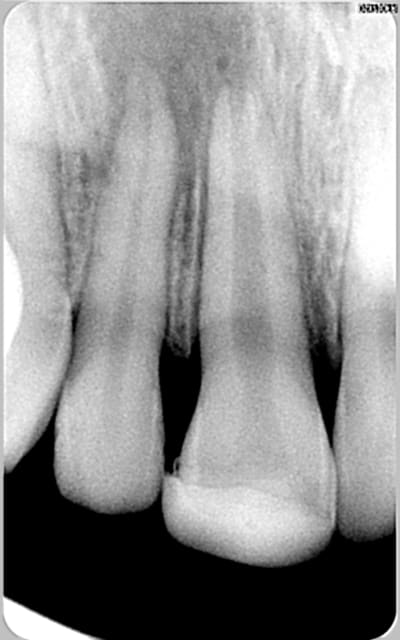

encore des radios,peut-etre assez moyen comme traitement...mais je vu pire...

les dernieres radios. patient en urgence ,abces... il voulait pas extraire la dent. j'ai lui bien explque et il a choisi de essayer de garder la dent. retrait,pas d'isolation avec la digue donc pas de tenon fibree,amalgam et screw post.traitement fait il ya 2 ans je crois.patient fidel de cabinet maintenent.